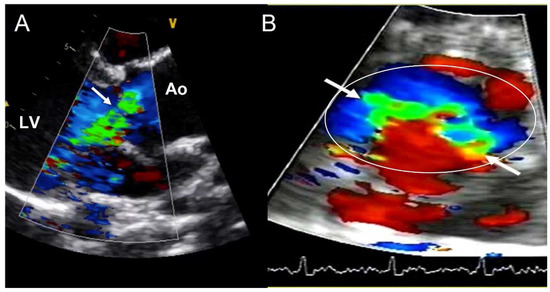

4.3. Aortic Regurgitation